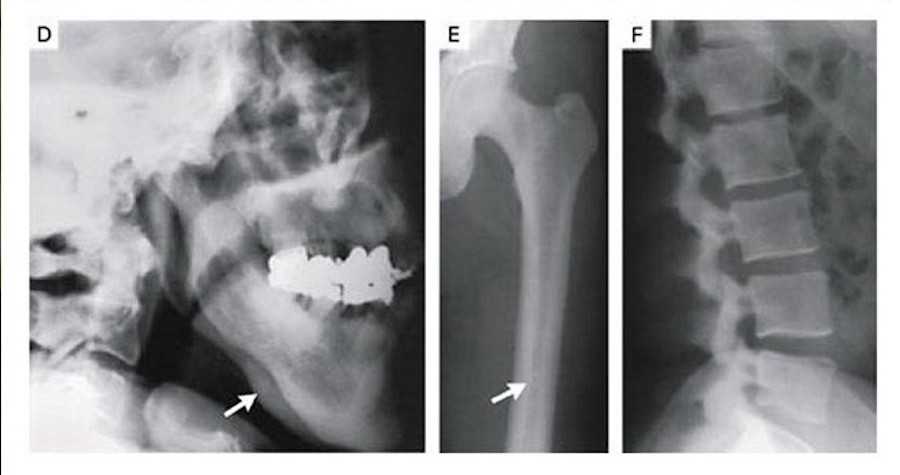

В 1994 году стала известна история о людях со сверхпрочным скелетом: в Коннектикуте (США) из страшной автокатастрофы водитель вышел без единого перелома. Рентгеновские снимки показали аномально плотные кости. Мужчину отправили в Йельский костный центр где обнаружилось, что его кости плотнее скелета обычного человека такого же возраста в восемь раз.

Высокая плотность костей из-за мутации в гене LRP5, которая обычно ведет к остеопорозу

(Фото: New England Journal of Medicine)

Позже выяснилось, что никто из его родных никогда ничего себе не ломал и не жаловался на ушибы. Исследования ДНК выявили мутацию в гене LRP5, сделавшую этих людей невероятно устойчивыми к различным повреждениям и ударам. Однако мужчина пожаловался, что ему никогда не удавалось держаться на воде, он всегда считал себя слишком тяжелым для плавания.

«С одной стороны, такие плотные кости менее ломкие, и человеку комфортно жить, осознавая, что риск получить переломы и травмы минимален. С другой стороны, такая плотность костей означает, что человек с большей вероятностью может утонуть, он менее плавучий, в отличие от того, у кого кости более полые», — объясняет Оксана Максименко, руководитель Центра высокоточного редактирования и генетических технологий для биомедицины ИБГ РАН.